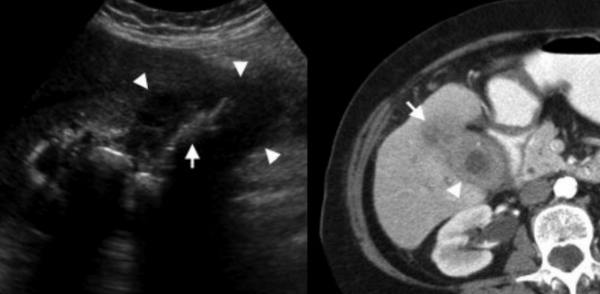

Сверху изображения пациента 62 лет с калькулезным холециститом. На УЗИ визуализируется стенки желчного пузыря растянутые, с субсерозным отеком (указано белыми стрелками) и в просвете желчного пузыря камень и взвесь. На КТ визуализируется переход воспалительного процесса с желчного пузыря на соседние ткани (перихолецистит).